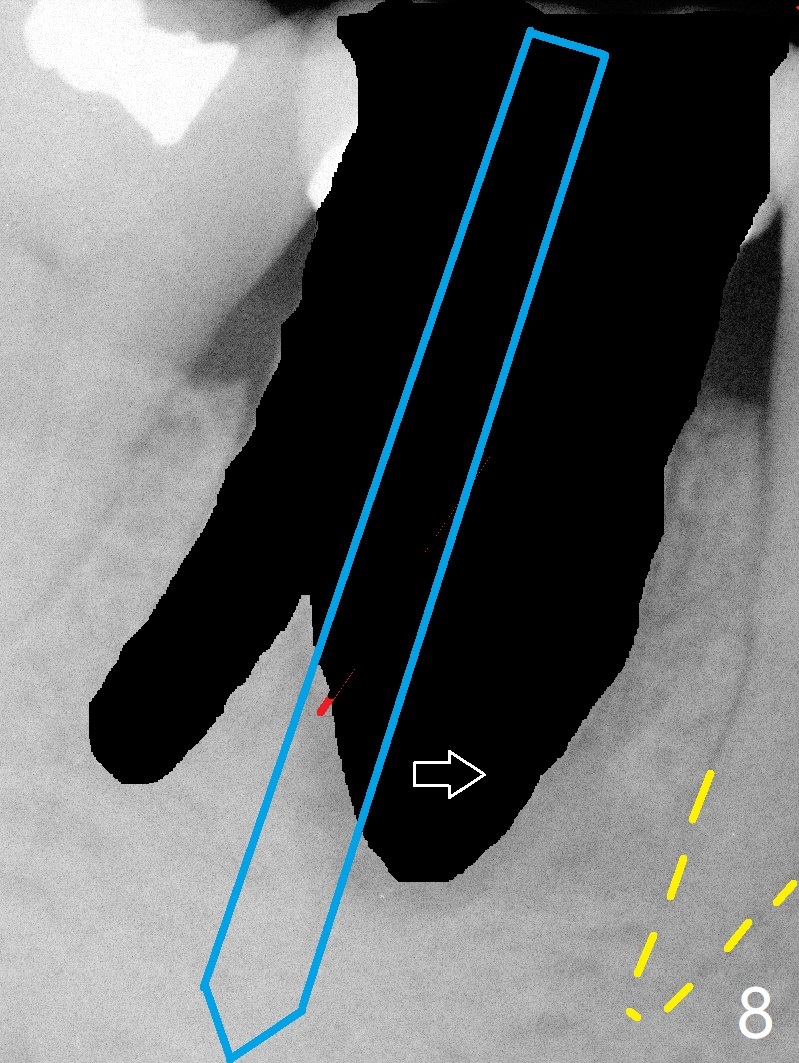

A 55-year-old woman has severe bone loss (Fig.1 with buccal and lingual fistulae) around the mesial (M in Fig.2) and distolingual (DL) roots. If there is a septum after extraction (Fig.3 S), osteotomy will be established in the septum to enhance primary stability (Fig.4). When the septum cannot be saved (Fig.5), osteotomy is to be initiated in the septal slope oblique (Fig.6 <). The osteotomy will be straightened once an entry is made (Fig.7). The initial osteotomy is slightly distal, since as osteotomy increases (Fig.8 blue), it tends to shift mesial (arrow). In addition, the apex of the 2nd bicuspid tilts distal (yellow dashed line). Depth of osteotomy is 20 mm (crest, Fig.9) or 18 mm (septum) so that 8 mm of the native bone can be obtained with 3 mm clearance from the Inferior Alveolar Canal (red dashed line). PRFx2 is required (seems not done).